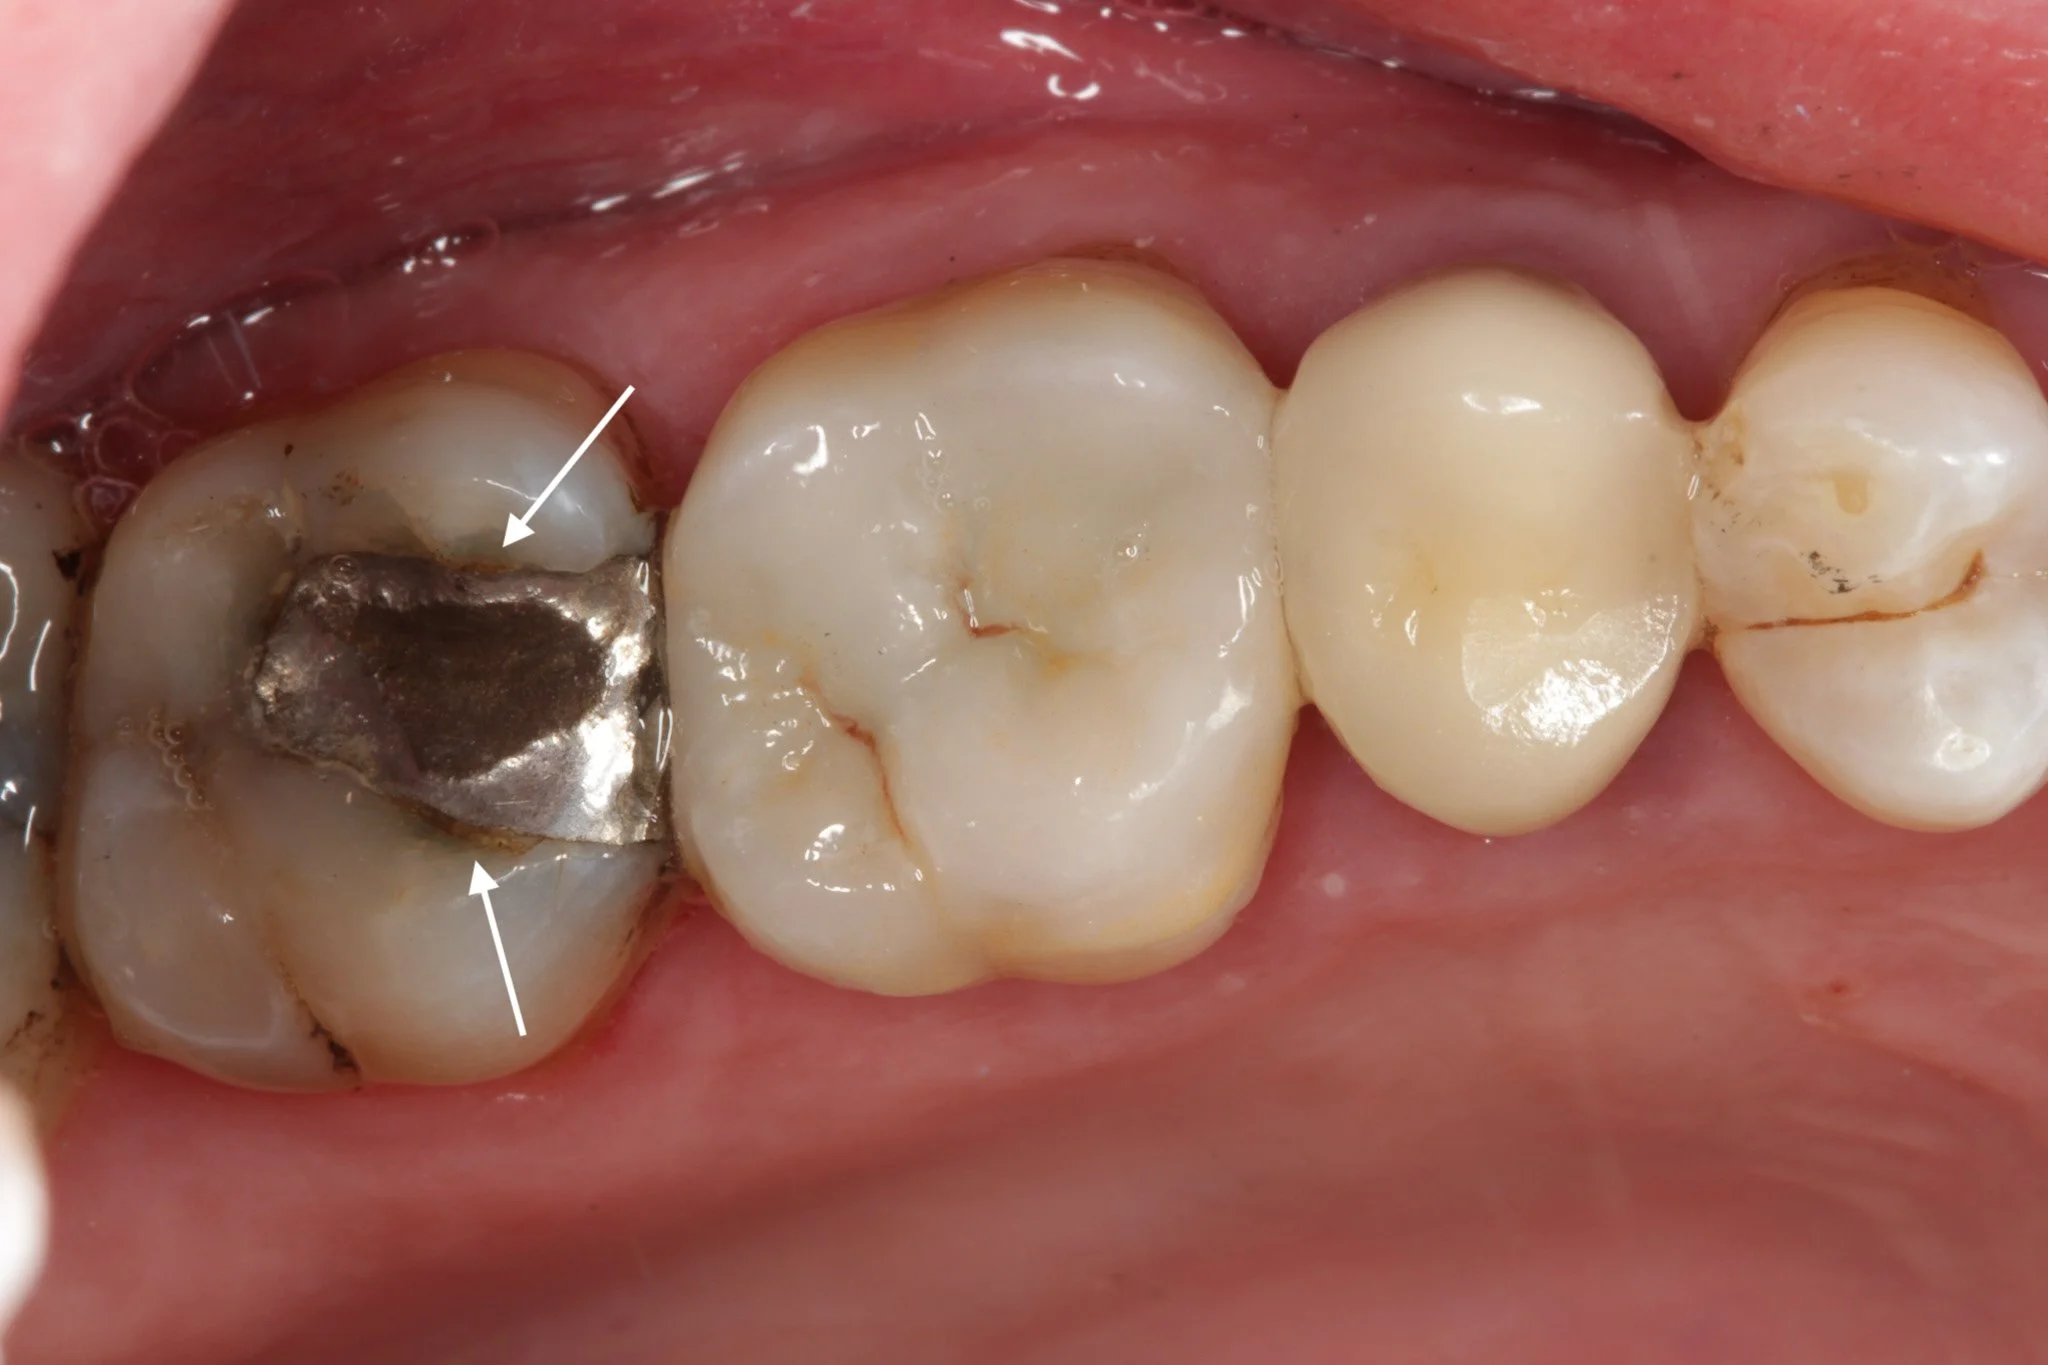

• Fractured fillings - This is when part of the filling breaks under pressure. It might be a small chip or a larger section missing.

• Debonding - This is when the filling loses its seal and starts to separate from the tooth. It may still look intact, but the bond underneath has failed, creating space for bacteria to enter and potentially cause decay.

• Loss of structural integrity - The filling is no longer properly supporting the tooth. This increases the risk of further fracture, sometimes of the tooth itself.